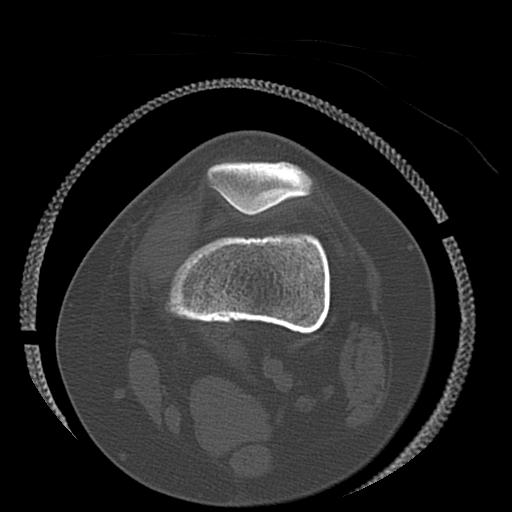

49554 3/13 膝 4R 3/16 4R 1/18 2R 78歳男性 膝蓋骨骨折